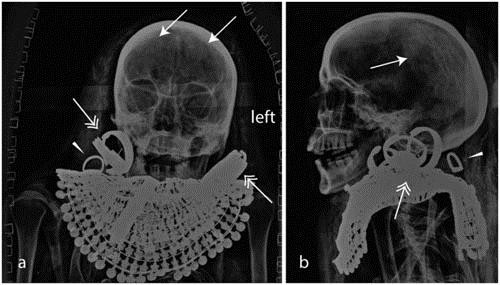

Raffaella Bianucci, tác giả chính của báo cáo và cộng sự sử dụng kỹ thuật chụp X-quang thế hệ mới và phương pháp phân tích vi lượng hóa học để tìm hiểu quy trình ướp xác.

Họ phát hiện cả hai vợ chồng đều trải qua một quá trình ướp xác chất lượng cao, trong đó có sử dụng những thành phần mang đặc tính chống vi khuẩn, chống côn trùng và nhựa thông nhập khẩu đắt tiền. Các bộ phận cơ thể của hai vợ chồng (cơ quan trong vùng bụng và ngực, bộ não, nhãn cầu mắt) đều được bảo quản rất tốt bằng muối natron sau gần 3.500 năm.